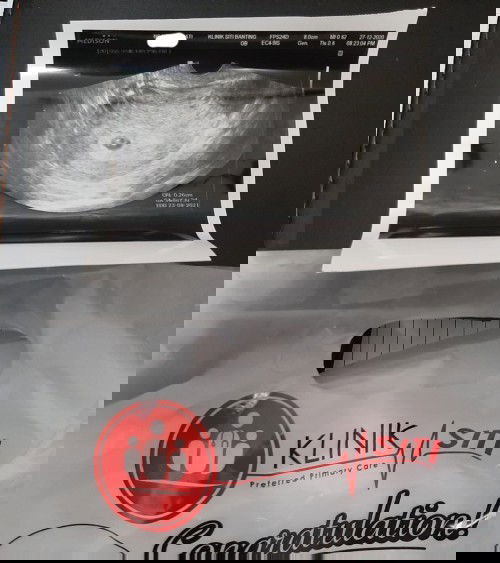

bila saya kata keluar darah suami terus bawa gie klinik swasta.bila scan perut tak nampak baby dan kantung,doc masukkan alat scan melalui faraj alhamdulilah nampak kantung dan baby..doc kata dh ada jantung baby,awk nk dengar tak sy kata "nak"..dgr jantung baby lega hati sy kandungan sy 5 minggu 6 hari.. kata doc normal ada spotting awal kehamilan dan doc bg ubat kuatkan rahim..